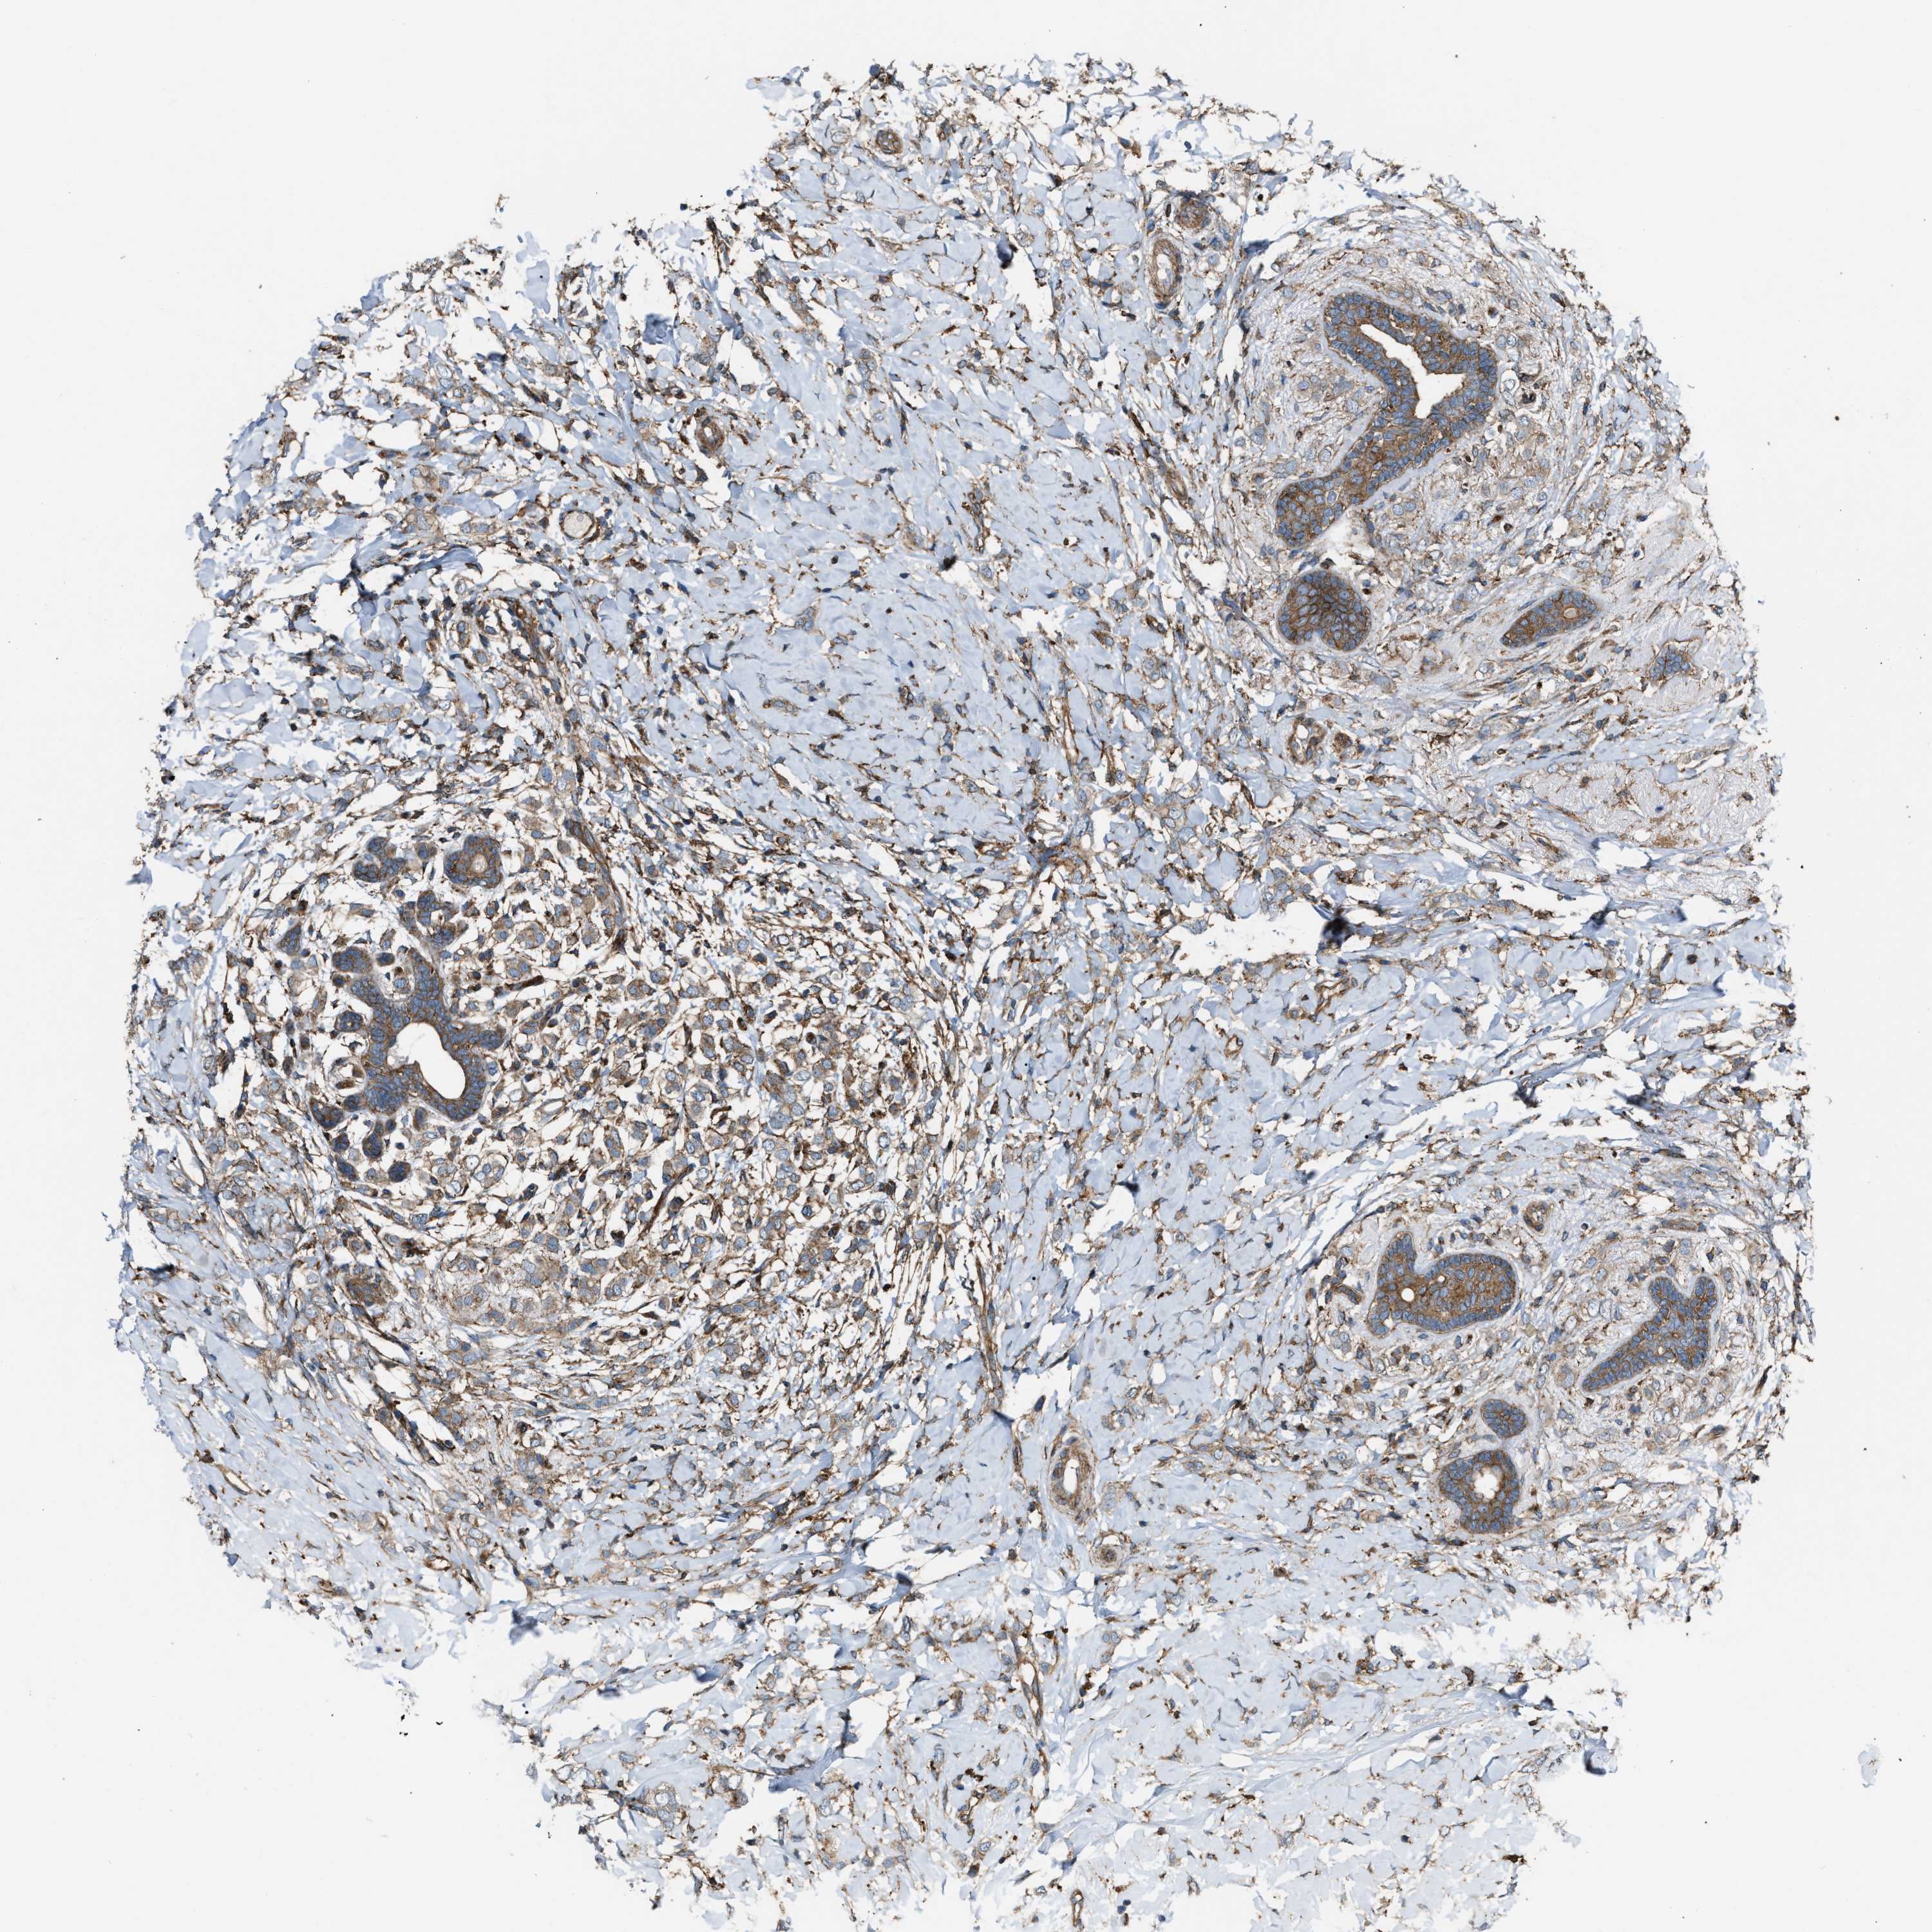

CANCER BREAST CANCER Show tissue menu

BRCA TCGA BRCA VALIDATION PROTEIN EXPRESSION

ANTIBODIES

AND

VALIDATION